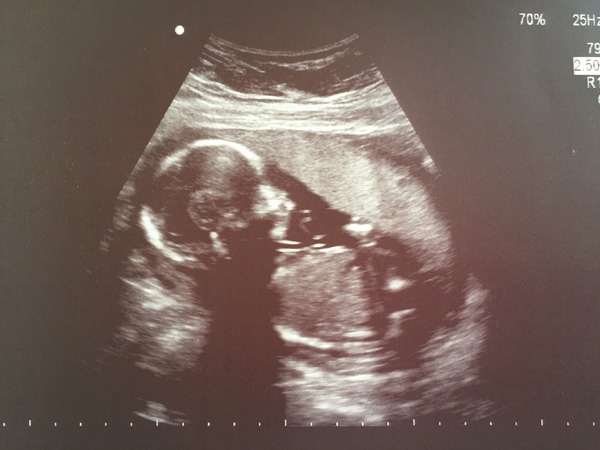

All present and correct with scan. Baby was very active, we saw it yawn and wave!

Decided this morning to find out the sex however baby had its legs tucked right up and the sonographer couldn't see, see we are still Team Yellow! Typical!

Ah Cola beautiful pic! 😁 You still have a nice surprise to look forward to at least!

Cola sounds like a good scan, and great pic.

cola great scan!! we also had a little yawn which was hilarious to see. Funny that babe wasn't playing ball...sounds like they are perhaps on the shy side Blush

Cola congrats, brilliant pic! And what a cheeky babe. I think s/he looks girly, but I am a terrible guesser, so don't buy any pink Grin